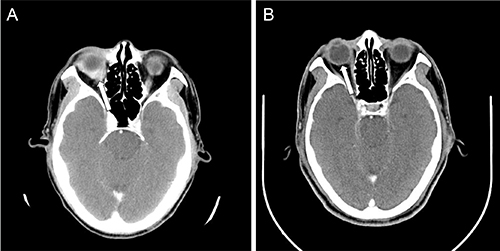

Figure 1: The CT scan of the brain with contrast showing (A) before treatment, the enhanced soft tissue infiltrates the right eyeball (arrow); and (B) after four cycles of R-CHOP, the tissue resolved with CR.